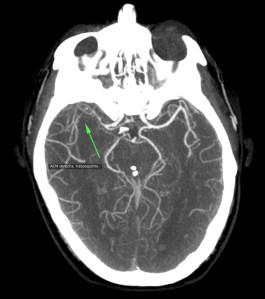

Se decide realizar Angio-TC.

El 85% de las hemorragias espontáneas en el espacio subaracnoideo son debidas a la ruptura de un aneurisma. Se deben a la evaginación de la íntima y la adventicia, la clave es la ausencia de lámina elástica interna y capa muscular. Se da en el 1% de la población y entre el 2-30% pueden ser múltiples. El 90% de los aneurismas cerebrales se localizan en la circulación anterior, los localizados en la ACM dan la típica imagen de hiperdensidad en las cisternas basares cuando se rompen.

Angiografía- TC: Se basa en la TC de cortes helicoidales. Aunque implica radiación para el paciente y requiere administración de contraste iodado intra-venoso (no requiere cateterización arterial), el hecho de que posea gran disponibilidad y sea una técnica rápida y fácil de llevar a cabo en pacientes enfermos, hace que se use como prueba de primera línea. Se puede realizar con cortes de 1 mm y realizaremos reconstrucciones para obtener imágenes como las de una angiografía (cine + MIP).